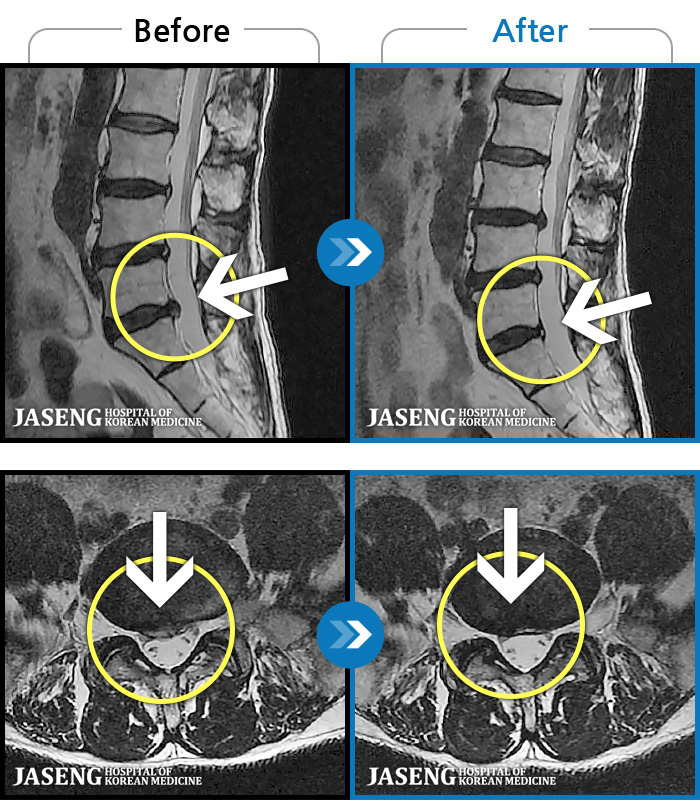

MRI ġ

MRI ũ ʸ Ȯϼ.